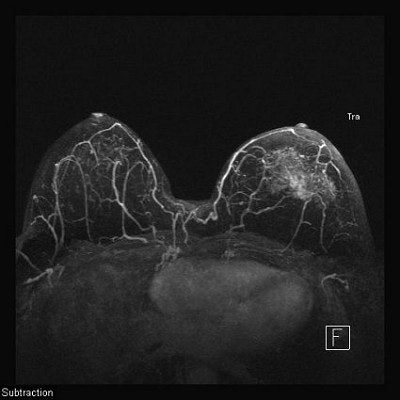

For lobular cancer diagnosis, Porter relies on a series of MIPs acquired over time to allow gadolinium contrast to leak, pool, and enhance tumor vessels.

The diffuse infiltrative nature of lobular carcinoma makes it difficult to detect. Two-minute (top), four-minute (middle), and thin-MIP (below) views demonstrate contrast enhancement in tumor tendrils over time. Images courtesy of Dr. Bruce Porter, First Hill Diagnostic Imaging.